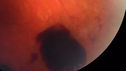

51 year old male with a broken vein in the left eye. His vision is pretty good. He has not noticed any vision change. You asked him to come here for further evaluation in the left eye. VA OD: sc20/63 PH20/25-2 NccJ1 VA OS: sc20/20 Patient had scatter laser to non-perfused retina and never had a vitreous hemorrhage (yet)

Coats' Disease -51 year old asymptomatic male450 views20/20 vision - had laser to non-perfusion because of proliferation.00000